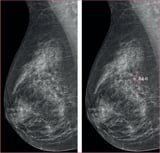

A recent study demonstrated that AI-supported mammography screenings identified 338 cancers, surpassing the 262 detected through traditional methods, and revealed a 24% increase in early-stage invasive cancer detection.

This enhanced detection rate marks a significant improvement over the control group's rate of five cancers per 1,000 screenings, all achieved without an increase in false positives.

The study emphasizes the critical role of AI in mammography, showcasing its ability to enhance clinical performance while maintaining accuracy.